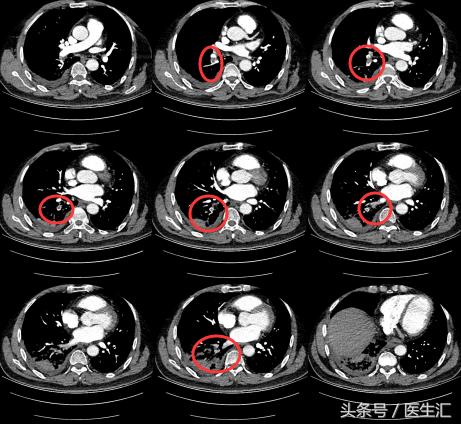

因为发现患者1 个月前有外伤手术史,那么是否可能有其他可能?所以我们给患者做了一个CTPA。

【关注】

每一个层面都有肺动脉的充盈缺损。

为明确患者肺栓塞的原因,所以做了彩超,结果如下图: